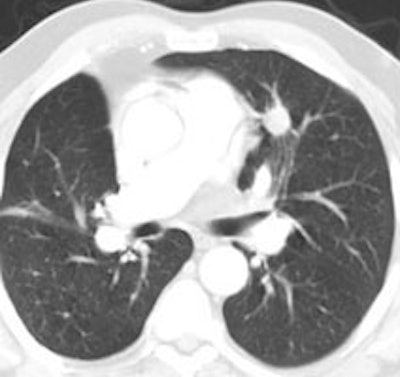

Example: The CT scan in this patient demonstrated a small nodule in the left upper lobe (black arrow). PET-FDG images demonstrate very intense accumulation of the tracer within the lesion (white arrow), which was a non-small cell lung cancer. (Case courtesy of H. Page McAdams MD, Department of Radiology, Duke University Medical Center) |